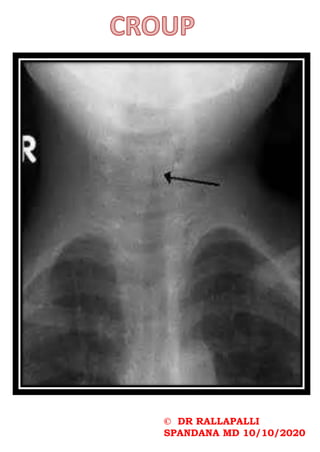

Steeple sign

Progressive narrowing of the upper airway